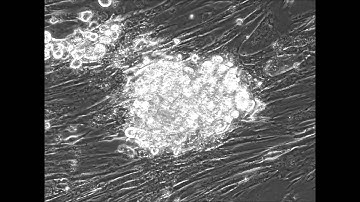

Reprogramming of fibroblasts to Assess Cardiomyocyte Subtypes | Protocol Preview